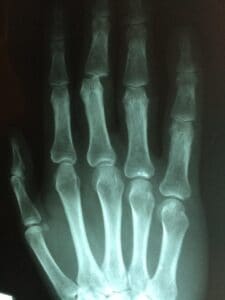

Joint pain in the pointer finger can arise from several conditions, including arthritis, tendinitis, or repetitive stress. Regardless of the cause, the pain can severely restrict mobility and affect your daily activities. Therefore, it is crucial to explore effective management strategies.